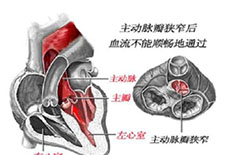

心脏瓣膜病及其他疾病

疾病介绍:心脏瓣膜病及其他疾病心脏瓣膜病就是指二尖瓣、三尖瓣、主动脉瓣和肺动脉瓣的瓣膜因风湿热、黏液变性、退行性改变、先天性畸形、缺血性坏死、感染或创…【详细】

心脏瓣膜病及其他疾病

疾病介绍:心脏瓣膜病及其他疾病心脏瓣膜病就是指二尖瓣、三尖瓣、主动脉瓣和肺动脉瓣的瓣膜因风湿热、黏液变性、退行性改变、先天性畸形、缺血性坏死、感染或创…【详细】

心脏瓣膜病及其他疾病

疾病介绍:心脏瓣膜病及其他疾病心脏瓣膜病就是指二尖瓣、三尖瓣、主动脉瓣和肺动脉瓣的瓣膜因风湿热、黏液变性、退行性改变、先天性畸形、缺血性坏死、感染或创…【详细】

心脏瓣膜病及其他疾病

疾病介绍:心脏瓣膜病及其他疾病心脏瓣膜病就是指二尖瓣、三尖瓣、主动脉瓣和肺动脉瓣的瓣膜因风湿热、黏液变性、退行性改变、先天性畸形、缺血性坏死、感染或创…【详细】

心脏瓣膜病及其他疾病

疾病介绍:心脏瓣膜病及其他疾病心脏瓣膜病就是指二尖瓣、三尖瓣、主动脉瓣和肺动脉瓣的瓣膜因风湿热、黏液变性、退行性改变、先天性畸形、缺血性坏死、感染或创…【详细】

心脏瓣膜病及其他疾病

疾病介绍:心脏瓣膜病及其他疾病心脏瓣膜病就是指二尖瓣、三尖瓣、主动脉瓣和肺动脉瓣的瓣膜因风湿热、黏液变性、退行性改变、先天性畸形、缺血性坏死、感染或创…【详细】

心脏瓣膜病及其他疾病

疾病介绍:心脏瓣膜病及其他疾病心脏瓣膜病就是指二尖瓣、三尖瓣、主动脉瓣和肺动脉瓣的瓣膜因风湿热、黏液变性、退行性改变、先天性畸形、缺血性坏死、感染或创…【详细】